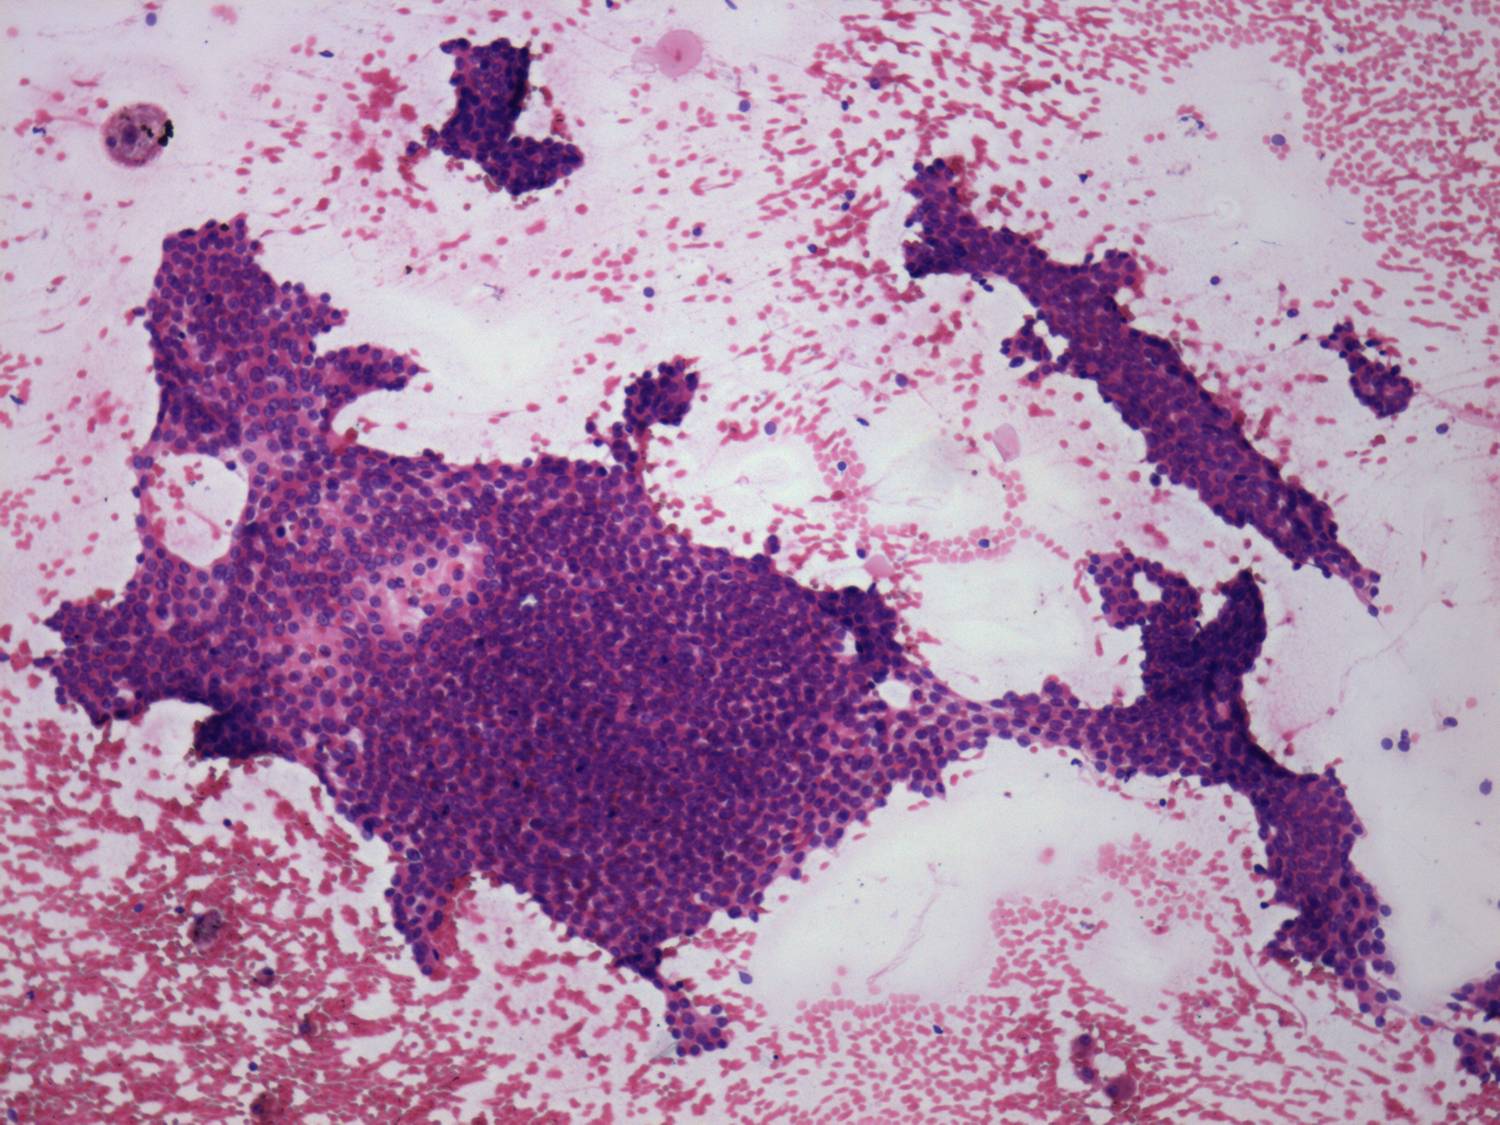

Subacute granulomatous thyroiditis - case 1777

Five months after the first examination (cytologic picture 3)

Pap-smear, 100x.   A papillary growth pattern is demonstrated.